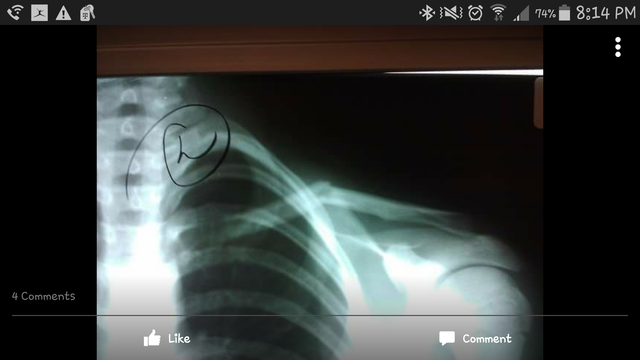

• Broke collarbone

Broke collarbone

The day we get back to school from Spud Harvest, that monday morning I was playing football with the boys and the ball got thrown low so I went to go dive for it and I landed right on top of my shoulder and I heard something snap or crack. So i stopped playing and I get to class and it hurt really bad so I went to the office and called my dad and mom. They came and got me and took me to the doctors, and turns out I broke my collarbone.